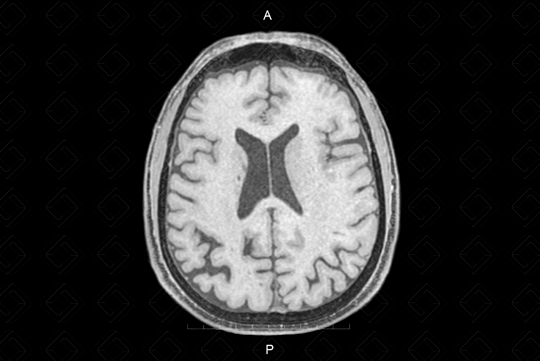

Texto alternativo para a imagem Figura 2. Créditos: Athena Hub/Medical Harbour

Descrição da figura 2: Imagem em T1 pós-contraste. A sequência T1 é a mais anatômica de todas as sequências no crânio.